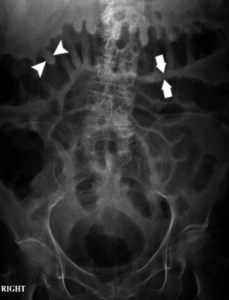

Klinis: anak 2 tahun, perut kembung dan sakit daerah perut. Dari hasil BNO datar di bawah ini, diagnosis